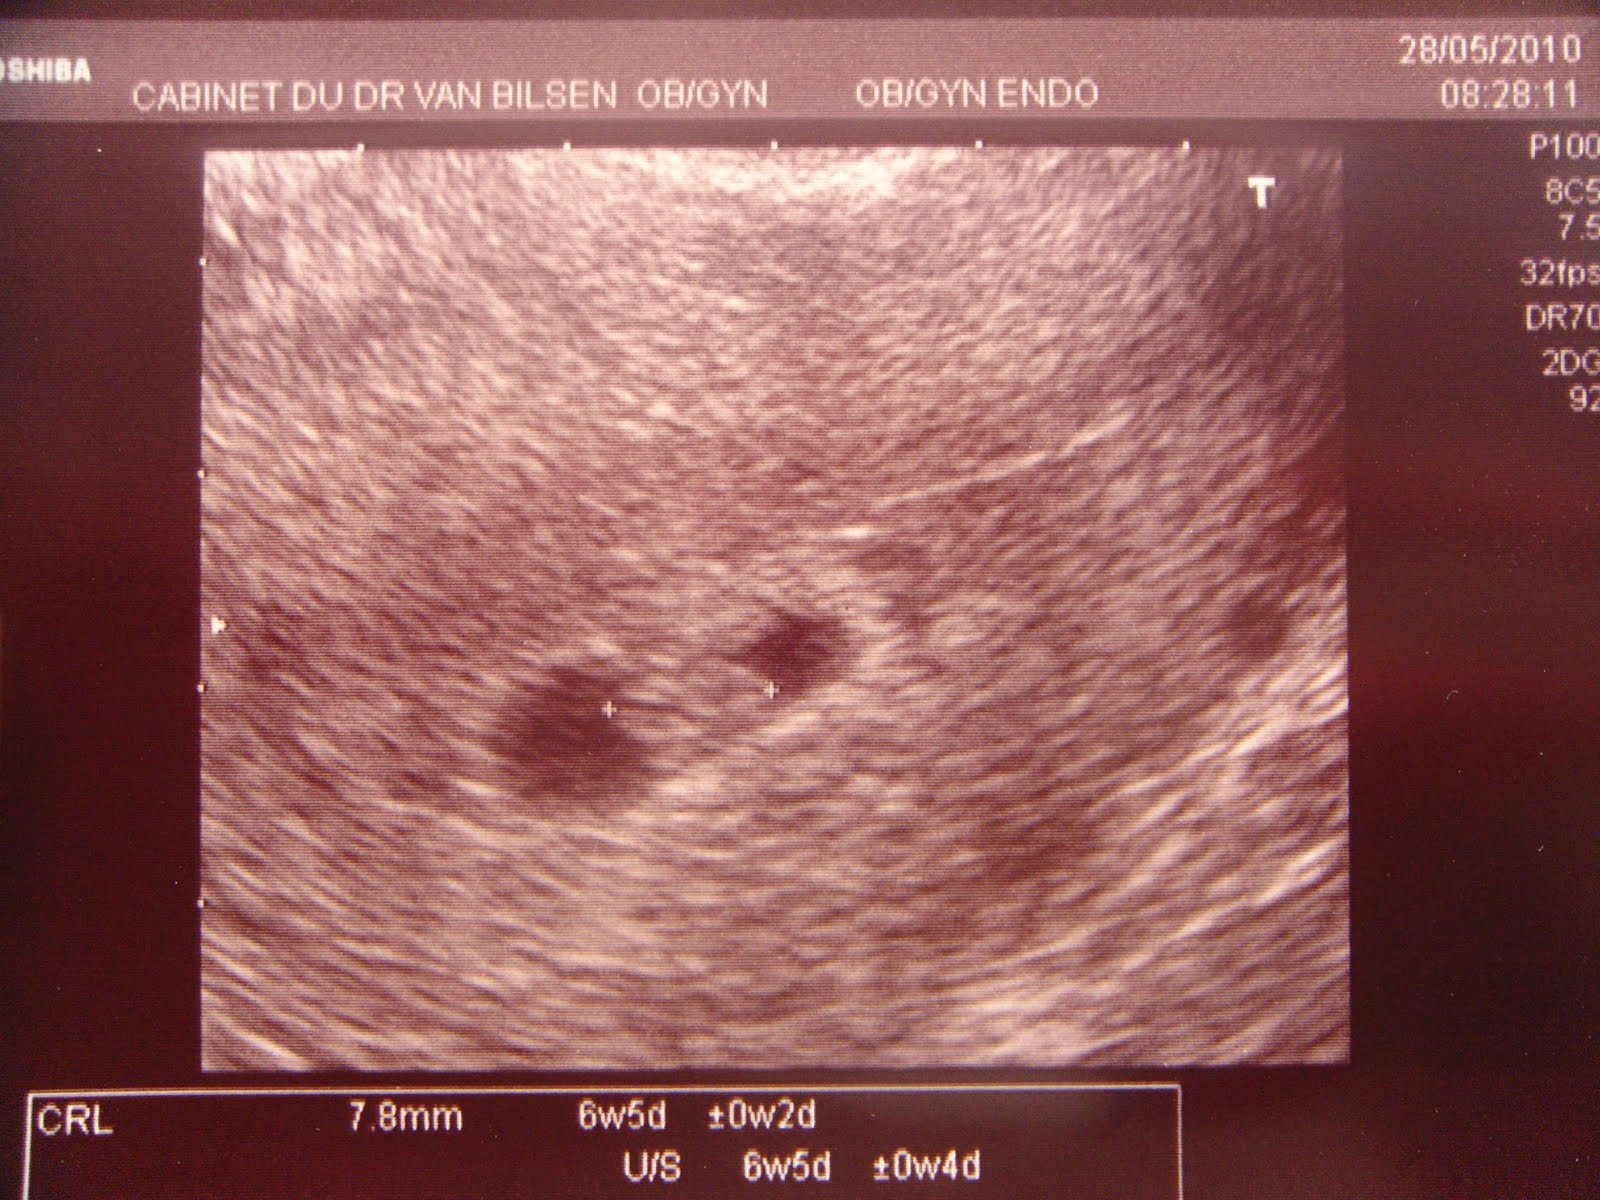

Je suis enceinte...

...e, este, é certamente o post que demonstra a felicidade de toda a família.

Esta foi a consulta de confirmação oficial mas, nós já sabíamos desde o dia da concepção!

Ontem, apanhei um susto pequenino e, nesta situação, não quis arriscar...só descansei quando hoje bem cedo vi e comprovei aquele coração a bater e a crescer dentro de mim. Ufa...que sensação de felicidade e alívio!

Decidimos em família partilhar este momento com as nossas famílias e, amigos, mesmo tendo o conhecimento de que uma gravidez aos 40 anos é considerada de alto risco. Sentimo-nos realizados e felizes e temos de viver um dia de cada vez com o optimismo necessário.